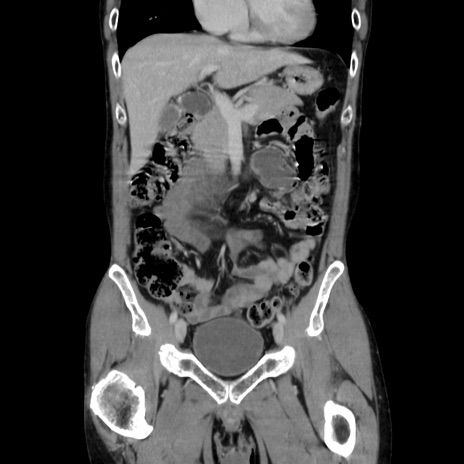

症例37(冠状断像)

【症例】40歳代 男性

【主訴】腹痛

【現病歴】4時間ほど前に電車に乗車中に臍部上より腹痛出現。徐々に増悪し起立困難となり、救急外来受診。生ものは数日食べていない。今朝お雑煮を食べた。

【身体所見】BT 36.8℃、BP 117/84mmHg、HR 91/min、SpO2 97%、苦悶様、腹部:臍上部広範囲圧痛あり、反跳痛±

【データ】WBC 8100、CRP 0.03